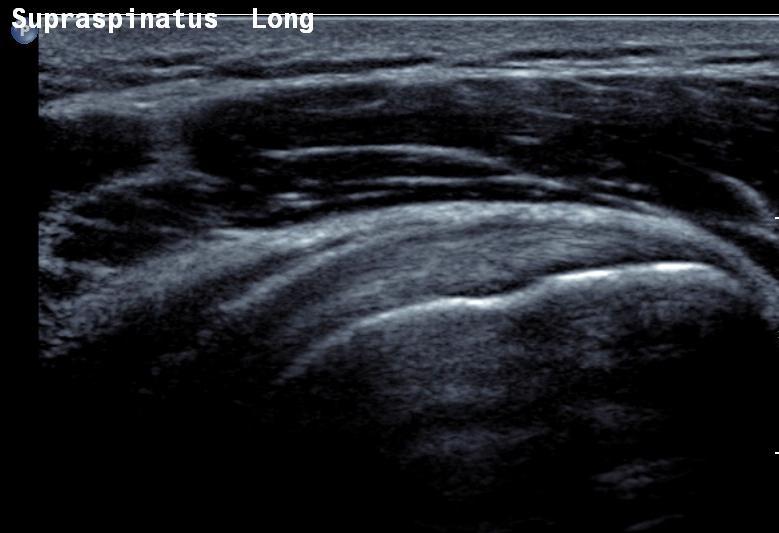

Διαγνωστικά κέντρα Καπανδρίτι, Βόρεια προάστια. Ακτινολογικό κέντρο Καπαδρίτι

Ακτινολογικό ιατρείο, ακτινολόγος Καπανδρίτι